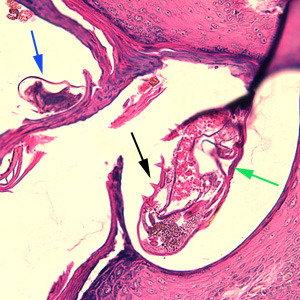

Case #244 – January, 2009

An 80-year-old resident of a long-term care facility presented with a skin condition manifesting as thick crusts over the skin accompanied by slight itching. The patient was originally treated for impetigo, with no resolution, and was ultimately admitted to the hospital for further testing. A skin biopsy was performed. The specimen was sectioned, stained with hematoxylin and eosin (H&E) and sent to a dermatopathologist for diagnostic assistance. Figures A–D show what was observed in the stained sections. Figures A and B were taken at 200x magnification. Figures C and D represent the same fields, respectively, taken at 400x magnification. What is your diagnosis? Based on what criteria?

Figure D